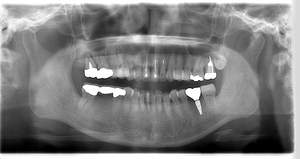

インプラント治療の症例3

レントゲン写真

- Befor

- After

| 年齢 | 50代・男性 |

|---|---|

| 主訴 | 左下7番 |

| 治療内容 | 右下7番インプラント埋入 |

| 治療費 | 合計:572,000円 診断料:55,000円 埋入料:165,000円 サージカルガイド:55,000円 静脈内鎮静麻酔:77,000円 仮歯:55,000円 上部構造(フルジルコニア):165,000円 (2023年1月現在) |

| 治療期間 | 約8ヶ月 |

| リスク・副作用 | リスク・副作用 |

| 治療方針 | 骨が十分にあるため、骨造成をすることなく埋入した。かみ合わせが強いので、負荷がかからないよう、夜寝るときにマウスピースをつけるよう指示をした。 |

| 担当者所見 | 左下6番7番のインプラントは他院で埋入しており、右下7番は抜歯したままで、かみ合わせの歯が落ちてきてしまうのでインプラントを埋入しました。 |